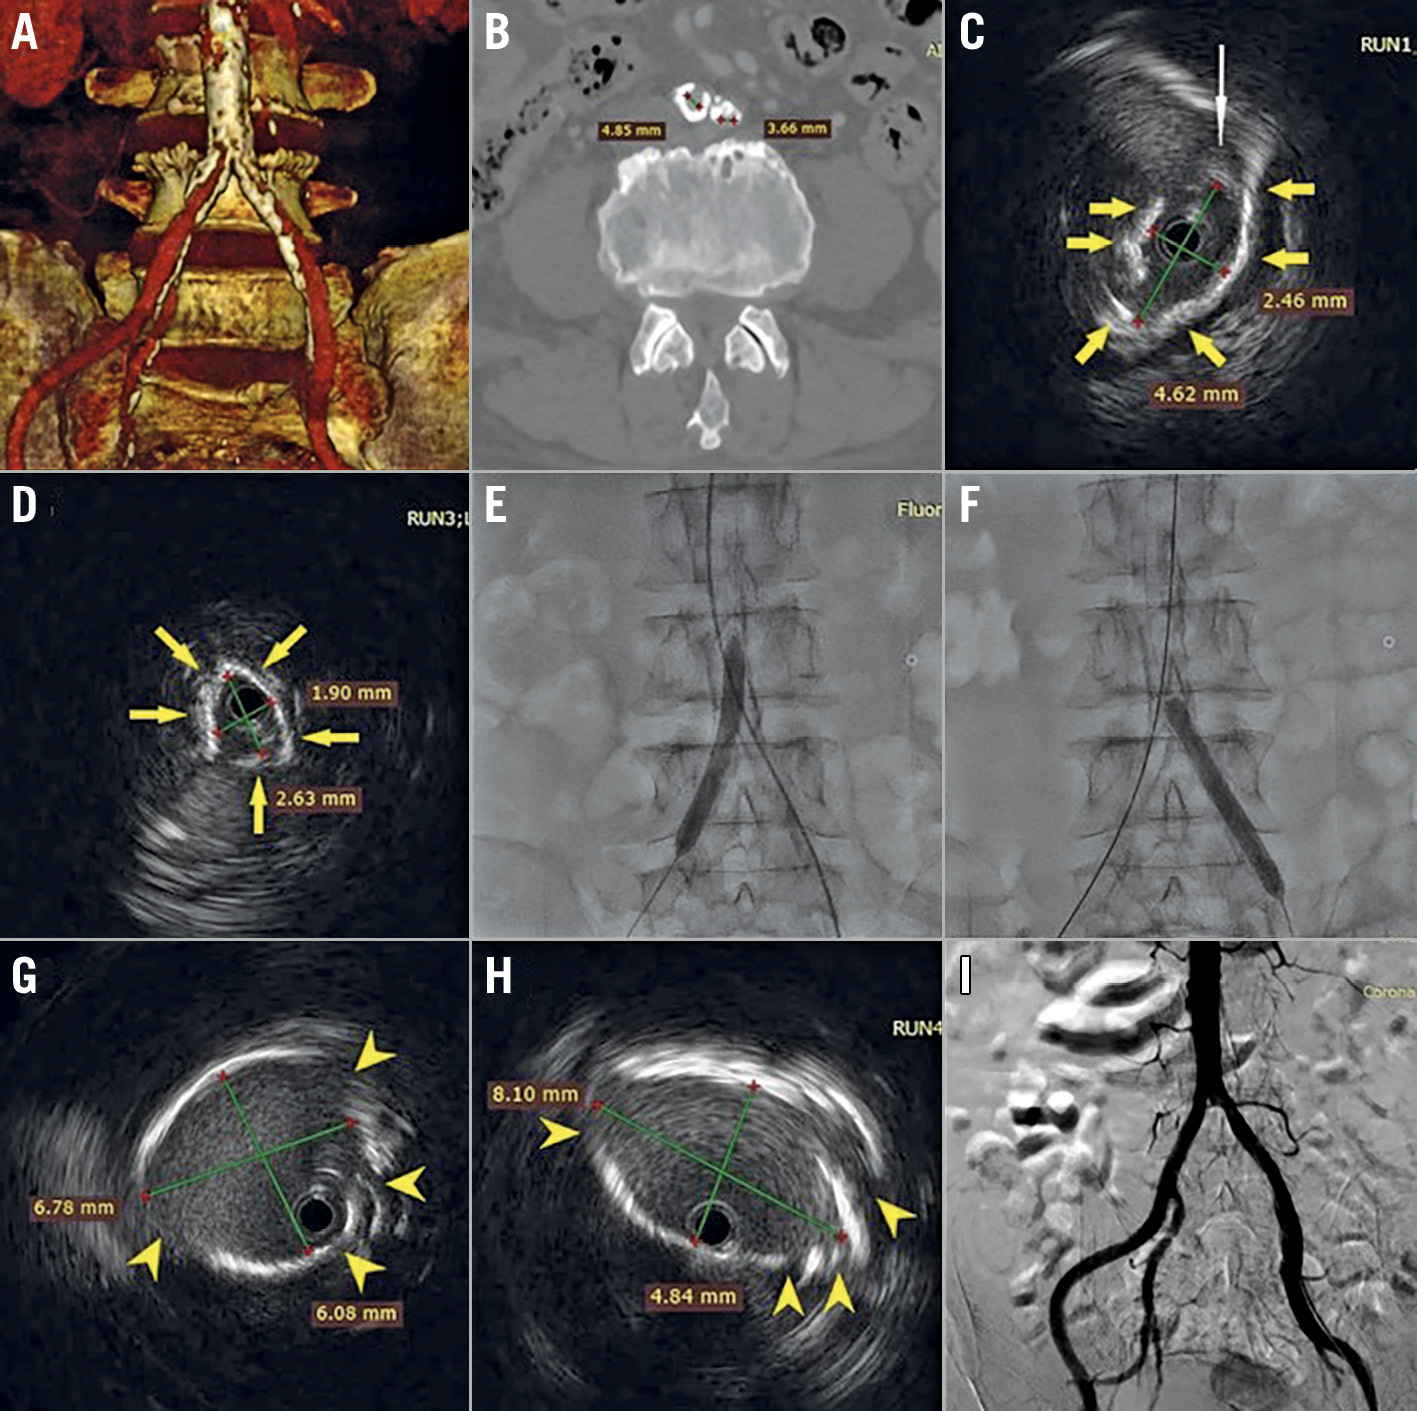

An 80-year-old male with chronic kidney disease (creatinine 200 µmol/L) presented with symptomatic severe aortic stenosis. The computed tomographic scan showed peripheral artery disease (PAD) with a heavily calcified distal aorta, and severely calcified stenoses of the right and left common iliac arteries (CIA), measuring, 4.9 mm and 3.7 mm, respectively (Panel A, Panel B). Transcatheter aortic valve implantation (TAVI) was chosen due to his age and elevated surgical risk. As the patient declined non-femoral approaches, we proceeded with transfemoral TAVI with vessel preparation using Shockwave Intravascular Lithotripsy (IVL) (Shockwave Medical, Santa Clara, CA, USA). IVL enables treatment of calcified stenoses by sonic pressure waves. Both superficial and deep calcium are disrupted with minimal impact on healthy tissue, achieving calcified plaque modification and increasing vessel compliance and size.

The femoral arteries were punctured under ultrasound guidance. A preprocedural aortoiliac angiogram was not performed in order to minimise contrast load and reduce the risk of acute kidney injury. An intravascular ultrasound (IVUS) (OptiCross™ 18 catheter; Boston Scientific, Marlborough, MA, USA), performed to help guide the lithotripsy procedure, confirmed CIA stenoses with napkin-ring calcifications (Panel C – IVUS image of the right common iliac artery, Panel D – IVUS image of the left common iliac artery, yellow arrows denote vessel calcification, white arrow denotes soft plaque). As the non-diseased external iliac artery diameter was approximately 7 mm, a 7×60 mm Shockwave balloon was selected. This was advanced over a 0.014-inch wire to the right CIA and inflated to 4 atm (lithotripsy delivery pressure). Four cycles of 30 pulses each were delivered and then two cycles were delivered to the left CIA (Panel E, Panel F) Repeat IVUS showed calcified plaque fractures with luminal gain (Panel G – IVUS image of the right common iliac artery after IVL, Panel H – IVUS image of the left common iliac artery after IVL, yellow arrowheads denote calcium fractures).

Apart from mild to moderate resistance during insertion of the 14 Fr expandable sheath from the right femoral artery, a 23 mm SAPIEN 3 valve (Edwards Lifesciences, Irvine, CA, USA) crossed the calcified right CIA inside the sheath without much difficulty and was successfully implanted under Sentinel™ (Boston Scientific) cerebral protection. The completion angiography showed no iliofemoral dissection with good flow (Panel I), and the femoral arteriotomy was closed with the ProGlide® (Abbott Laboratories, Abbott Park, IL, USA) pre-closure technique. IVUS-guided IVL can be used to facilitate transfemoral TAVI in patients with calcified PAD and is likely safer than using non-compliant or cutting balloons to dilate severely calcified iliofemoral vessels.